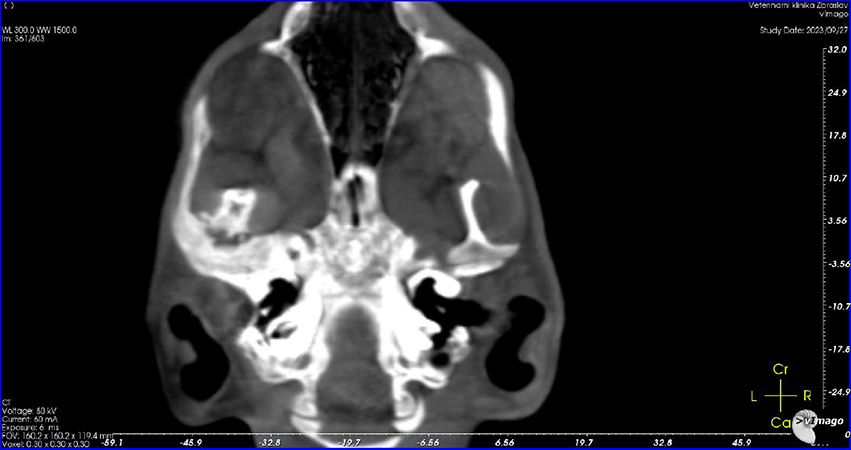

27.9.2023

Leo absolvuje nové CT vyšetření. Je zřejmé, že oproti původní diagnóze (špatně zhojené poškození měkkých tkání), je z nových snímků jasně patrné, že Leo má špatně zhojenou zlomeninu spojení spodní čelisti a podočnicového oblouku na levé straně, což je důvod, proč se mu pusinka opět zavřela. Je nutná operace. Po krátké konzultaci v Nuslích Linda domlouvá, aby Lea odoperovali akutně na Zbraslavi. Dostává zprávu, 3D model i CT snímky do mailu.